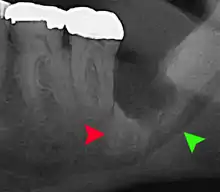

Coronectomy of impacted wisdom tooth post-op xray showing root remnants (red arrow) and inferior alveolar nerve (green arrow)

Coronectomy is a procedure where the crown of the impacted wisdom tooth is removed, but the roots are intentionally left in place. It is indicated when there is no disease of the dental pulp or infection around the crown of the tooth, and there is a high risk of inferior alveolar nerve injury.[31]

Coronectomy, while lessening the immediate risk to the inferior alveolar nerve function has its own complication rates and can result in repeated surgeries. Between 2.3% and 38.3% of roots loosen during the procedure and need to be removed and up to 4.9% of cases require reoperation due to persistent pain, root exposure or persistent infection. The roots have also been reported to migrate in 13.2% to 85.9% of cases.[31]